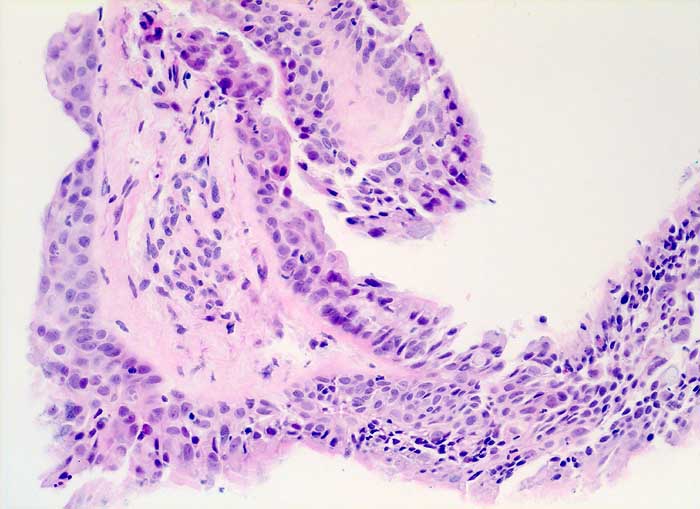

PathoPic ID 6038 - strahleninduzierte Kernatypien

strahleninduzierte Kernatypien

Therapiefolgen

Bronchus

Lunge, Mediastinum mit Thymus

Ausgeprägte Kernpolymorphie und Kernvergrösserung des respiratorischen Epithels bei erhaltener Kern-Zytoplasmarelation.

NSCLC neoadjuvante Therapie

Histologie

200